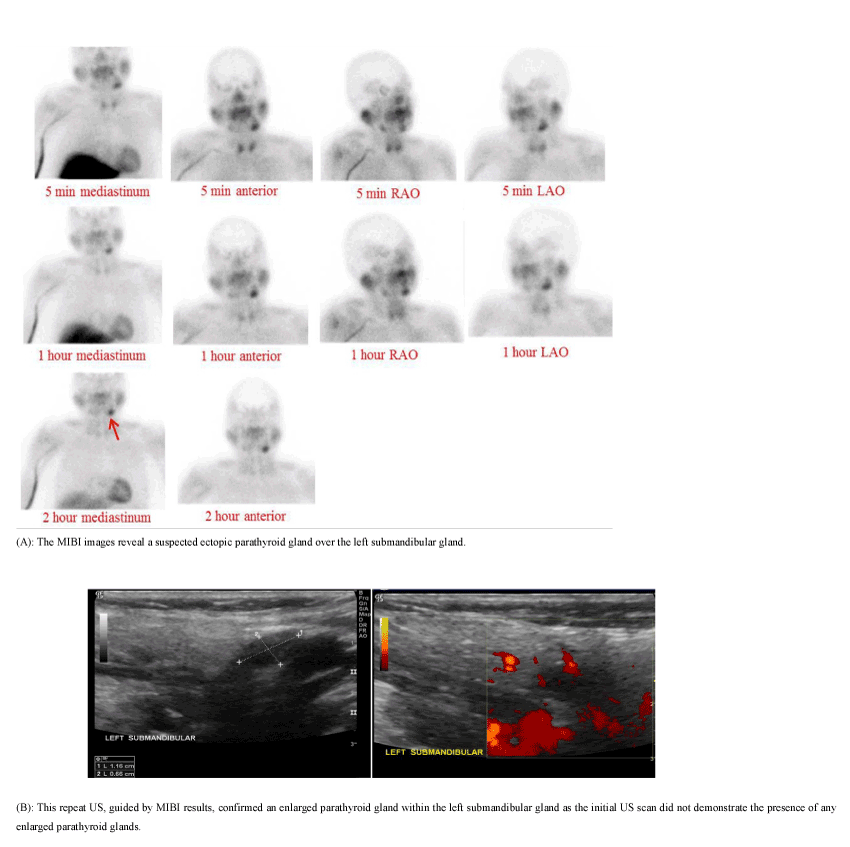

The limitations of US scans include: 1) operator-dependent analyses and 2) the inability to detect ectopic parathyroid glands (Figure 7).

Figure 7. A 63-year-old female presented with a PTH level of 90.2 pg/ml and a calcium level of 10.2 mg/dl.